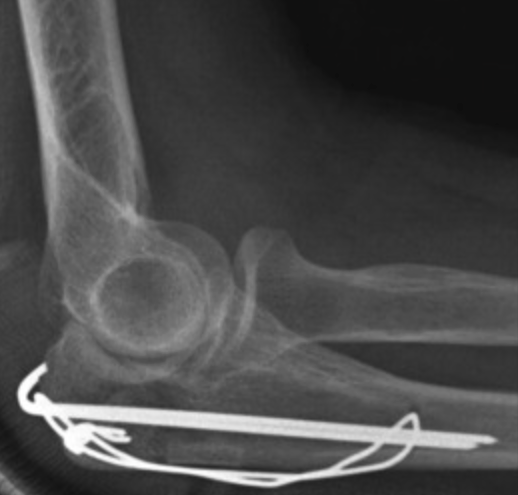

Olecranon Fractures

Olecranon fractures disrupt the extensor mechanism of the elbow — the triceps muscle pulls the proximal fragment proximally, preventing active elbow extension. Displaced fractures require surgical fixation:

- Tension band wiring (TBW): The traditional technique — two K-wires and a figure-of-eight wire convert the tensile force of the triceps into compression across the fracture. Highly effective but high implant prominence/irritation rates requiring later removal.